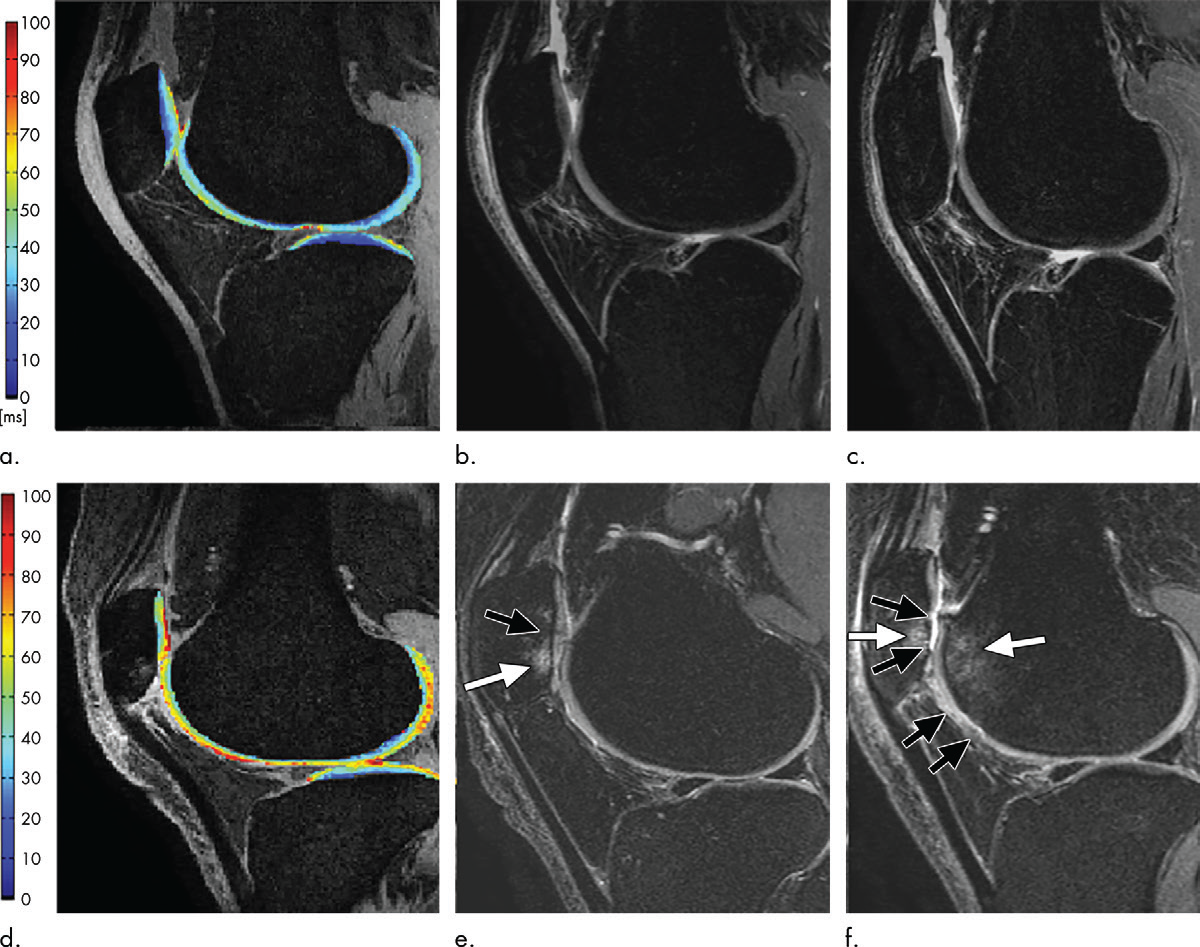

(1)关键技术解析

- T2 mapping:通过T2弛豫时间反映软骨基质状态——胶原纤维排列紊乱、含水量增加时,T2值升高。在糖尿病患者中,即使软骨形态正常,T2值也可能升高(图5),提示代谢因素对软骨的早期影响;

T1ρ成像:通过旋转坐标系下的T1弛豫时间评估蛋白多糖含量——蛋白多糖丢失时,T1ρ值升高,且基线T1ρ值可预测膝/髋OA进展(图6);

dGEMRIC:静脉注射含钆造影剂后,造影剂与软骨基质中带负电的蛋白多糖竞争结合位点,蛋白多糖丢失区域的造影剂摄取增加,T1值降低。该技术已用于发育性髋关节发育不良患者的术前评估,dGEMRIC指数异常的关节术后效果较差(图7)。

(2)临床转化前景

定量MRI的核心价值在于早期OA诊断与治疗监测。例如,T2 mapping与T1ρ成像可用于DMOAD临床试验,评估药物对软骨基质的保护作用;加速序列(如6分钟T2 mapping+形态学联合序列)的发展,已使其逐步走向临床常规应用。